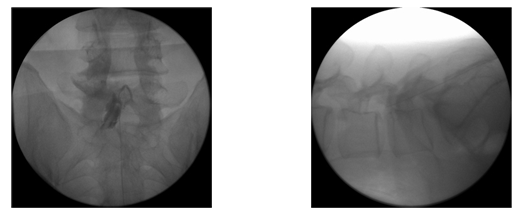

¼ö»ó ÈÄ ¾à 2ÁÖ°£ ħ»ó ¾ÈÁ¤°¡·á, Àû±ØÀû º¸Á¸Àû Ä¡·á ÈÄ¿¡µµ ÅëÁõÀÌ È£ÀüµÇÁö ¾Ê°í ôÃß»À°¡ °è¼Ó ÁÖÀú¾ÉÀ¸¸é, ±¹¼Ò ¸¶ÃëÇÏ¿¡ ÁÖÀú¾ÉÀº ôÃß»À¿¡ ±½Àº ¹Ù´ÃÀ» »ðÀÔÇÏ¿© °ñÀýºÎÀ§¿¡ ¹Ð°¡·ç ¹ÝÁ× °°Àº '°ñ ½Ã¸àÆ®'¸¦ ÁÖÀÔÇÏ¿© ¼öºÐ ÈÄ ´Ü´ÜÈ÷ ±»°Ô ¸¸µé¾î °ñÀýºÎÀ§¸¦ °íÁ¤ÇÏ¿© ÅëÁõ ¼Ò½Ç°ú Ãß°¡ ¾Ð¹ÚÀ» ¹æÁöÇϰíÀÚ ÇÏ´Â ½Ã¼úÀ̸ç, ½Ã¼ú½Ã°£Àº ¾à 20ºÐ Á¤µµ ¼Ò¿äµÇ¸ç °ñ´Ù°øÁõÀÌ ÀÖ´Â °æ¿ì¿¡´Â °ÅÀÇ ÅëÁõÀÌ ¾ø½À´Ï´Ù.